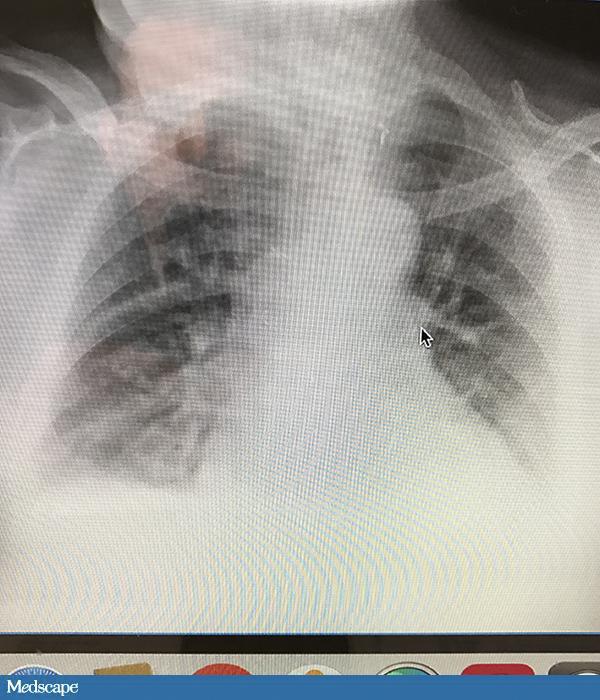

79 岁男性,病史复杂,包括心脏骤停、气管造口术后呼吸衰竭、经皮胃造口术置管(PEG)、慢性阻塞性肺疾病和糖尿病。近期患者从急性护理医院转入一家看护机构。转入后 6 天,患者出现间歇性干咳。生命体征平稳。无发热,呼吸节律正常,氧饱和度无变化。听诊闻及双肺底部湿罗音。便携式胸片示“肺右上叶轻微渗出”。患者白细胞为 12100 /µL,并未偏离正常值。医生开处万古霉素和头孢他啶 7 天。抗生素使用管理部门人员 48 小时后看到病例,此时应给出怎样的建议?

患者无发热、脓痰、呼吸急促或氧饱和度变化,诊断肺炎的证据不够。肺炎的诊断需要结合临床特征、实验室检查和放射科结果,不能只基于胸片发现就下诊断。如果患者发生肺炎,应该是医院内感染,所以没有必要增加非典型病菌的覆盖。如果确实是肺炎,且没有培养出甲氧西林耐药的金黄色葡萄球菌,停掉万古霉素是合理的处理。但缺少微生物诊断时,应使用覆盖假单胞菌的药物治疗一个周期。